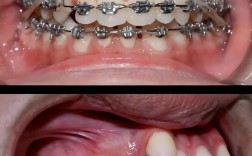

- 暴露种植体: 在一期手术(种植体植入)后,种植体通常被完全埋在牙龈组织下,以保护它在骨结合期间不受干扰,二期手术需要切开牙龈,移除覆盖在种植体顶部的牙龈组织,使种植体穿龈部分暴露出来。

- 连接基台: 暴露种植体后,医生会将一个基台拧入或粘接在种植体的顶部,基台是一个中间连接件,它起到了桥梁的作用:

- 形成牙龈袖口: 在基台周围,医生会精心塑形牙龈组织,使其紧密地包裹住基台,形成一个类似天然牙牙龈的“袖口”结构,这对于美观、清洁以及防止食物残渣进入种植体周围至关重要。